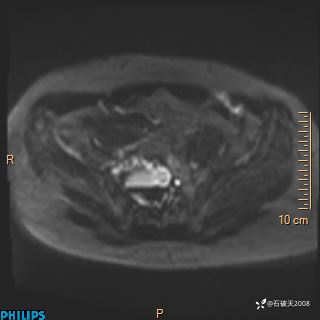

2023年3月份MRI影像

增强轴位